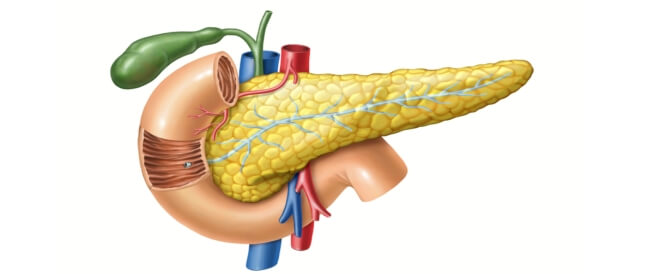

البنكرياس

الوصف: غدة تقع خلف المعدة

الوظائف

:إفراز إنزيمات هاضمة مثل

.الأميلاز: لتفكيك النشويات

.الليباز: لهضم الدهون

.التريبسين: لتفكيك البروتينات

.إفراز هرمونات مثل الأنسولين والجلوكاجون لتنظيم مستويات السكر في الدم